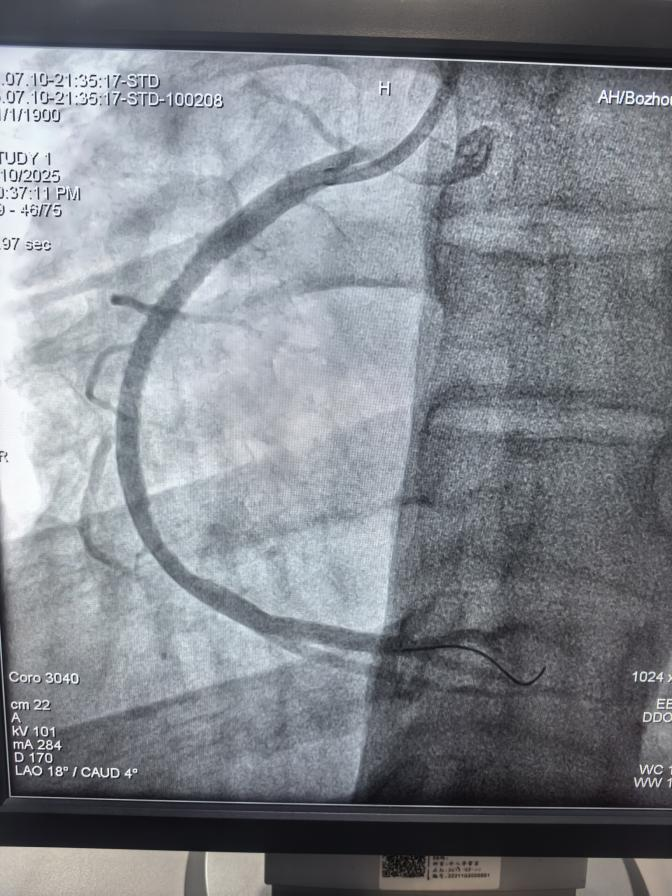

患者馮先生身高170cm,體重95kg,體型較為肥胖,平時(shí)作息不規(guī)律,長期抽煙、飲酒、熬夜,當(dāng)天突發(fā)心前區(qū)疼痛持續(xù)不能緩解,伴有大汗淋漓、煩躁不安,通過呼叫120救護(hù)車送至我院胸痛中心。心血管病科二病區(qū)介入醫(yī)生給他做了急診冠脈造影檢查,顯示右冠狀動(dòng)脈近段急性完全閉塞。經(jīng)過手術(shù)醫(yī)生積極有序的救治,順利開通閉塞血管后,在血管內(nèi)超聲指引下精確植入一枚藥物洗脫支架,植入后血流恢復(fù)良好,馮先生癥狀明顯改善,生命體征逐漸平穩(wěn)。術(shù)后身體恢復(fù)良好,于7月20日順利出院。

支架植入后,血管流通